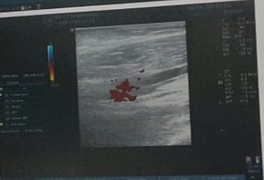

Ngày 17/3, Bệnh viện Nhân dân 115 phẫu thuật vi phẫu cứu 4 ngón tay bị đứt lìa hoàn toàn cho nam bệnh nhân gặp tai nạn máy cắt giấy.